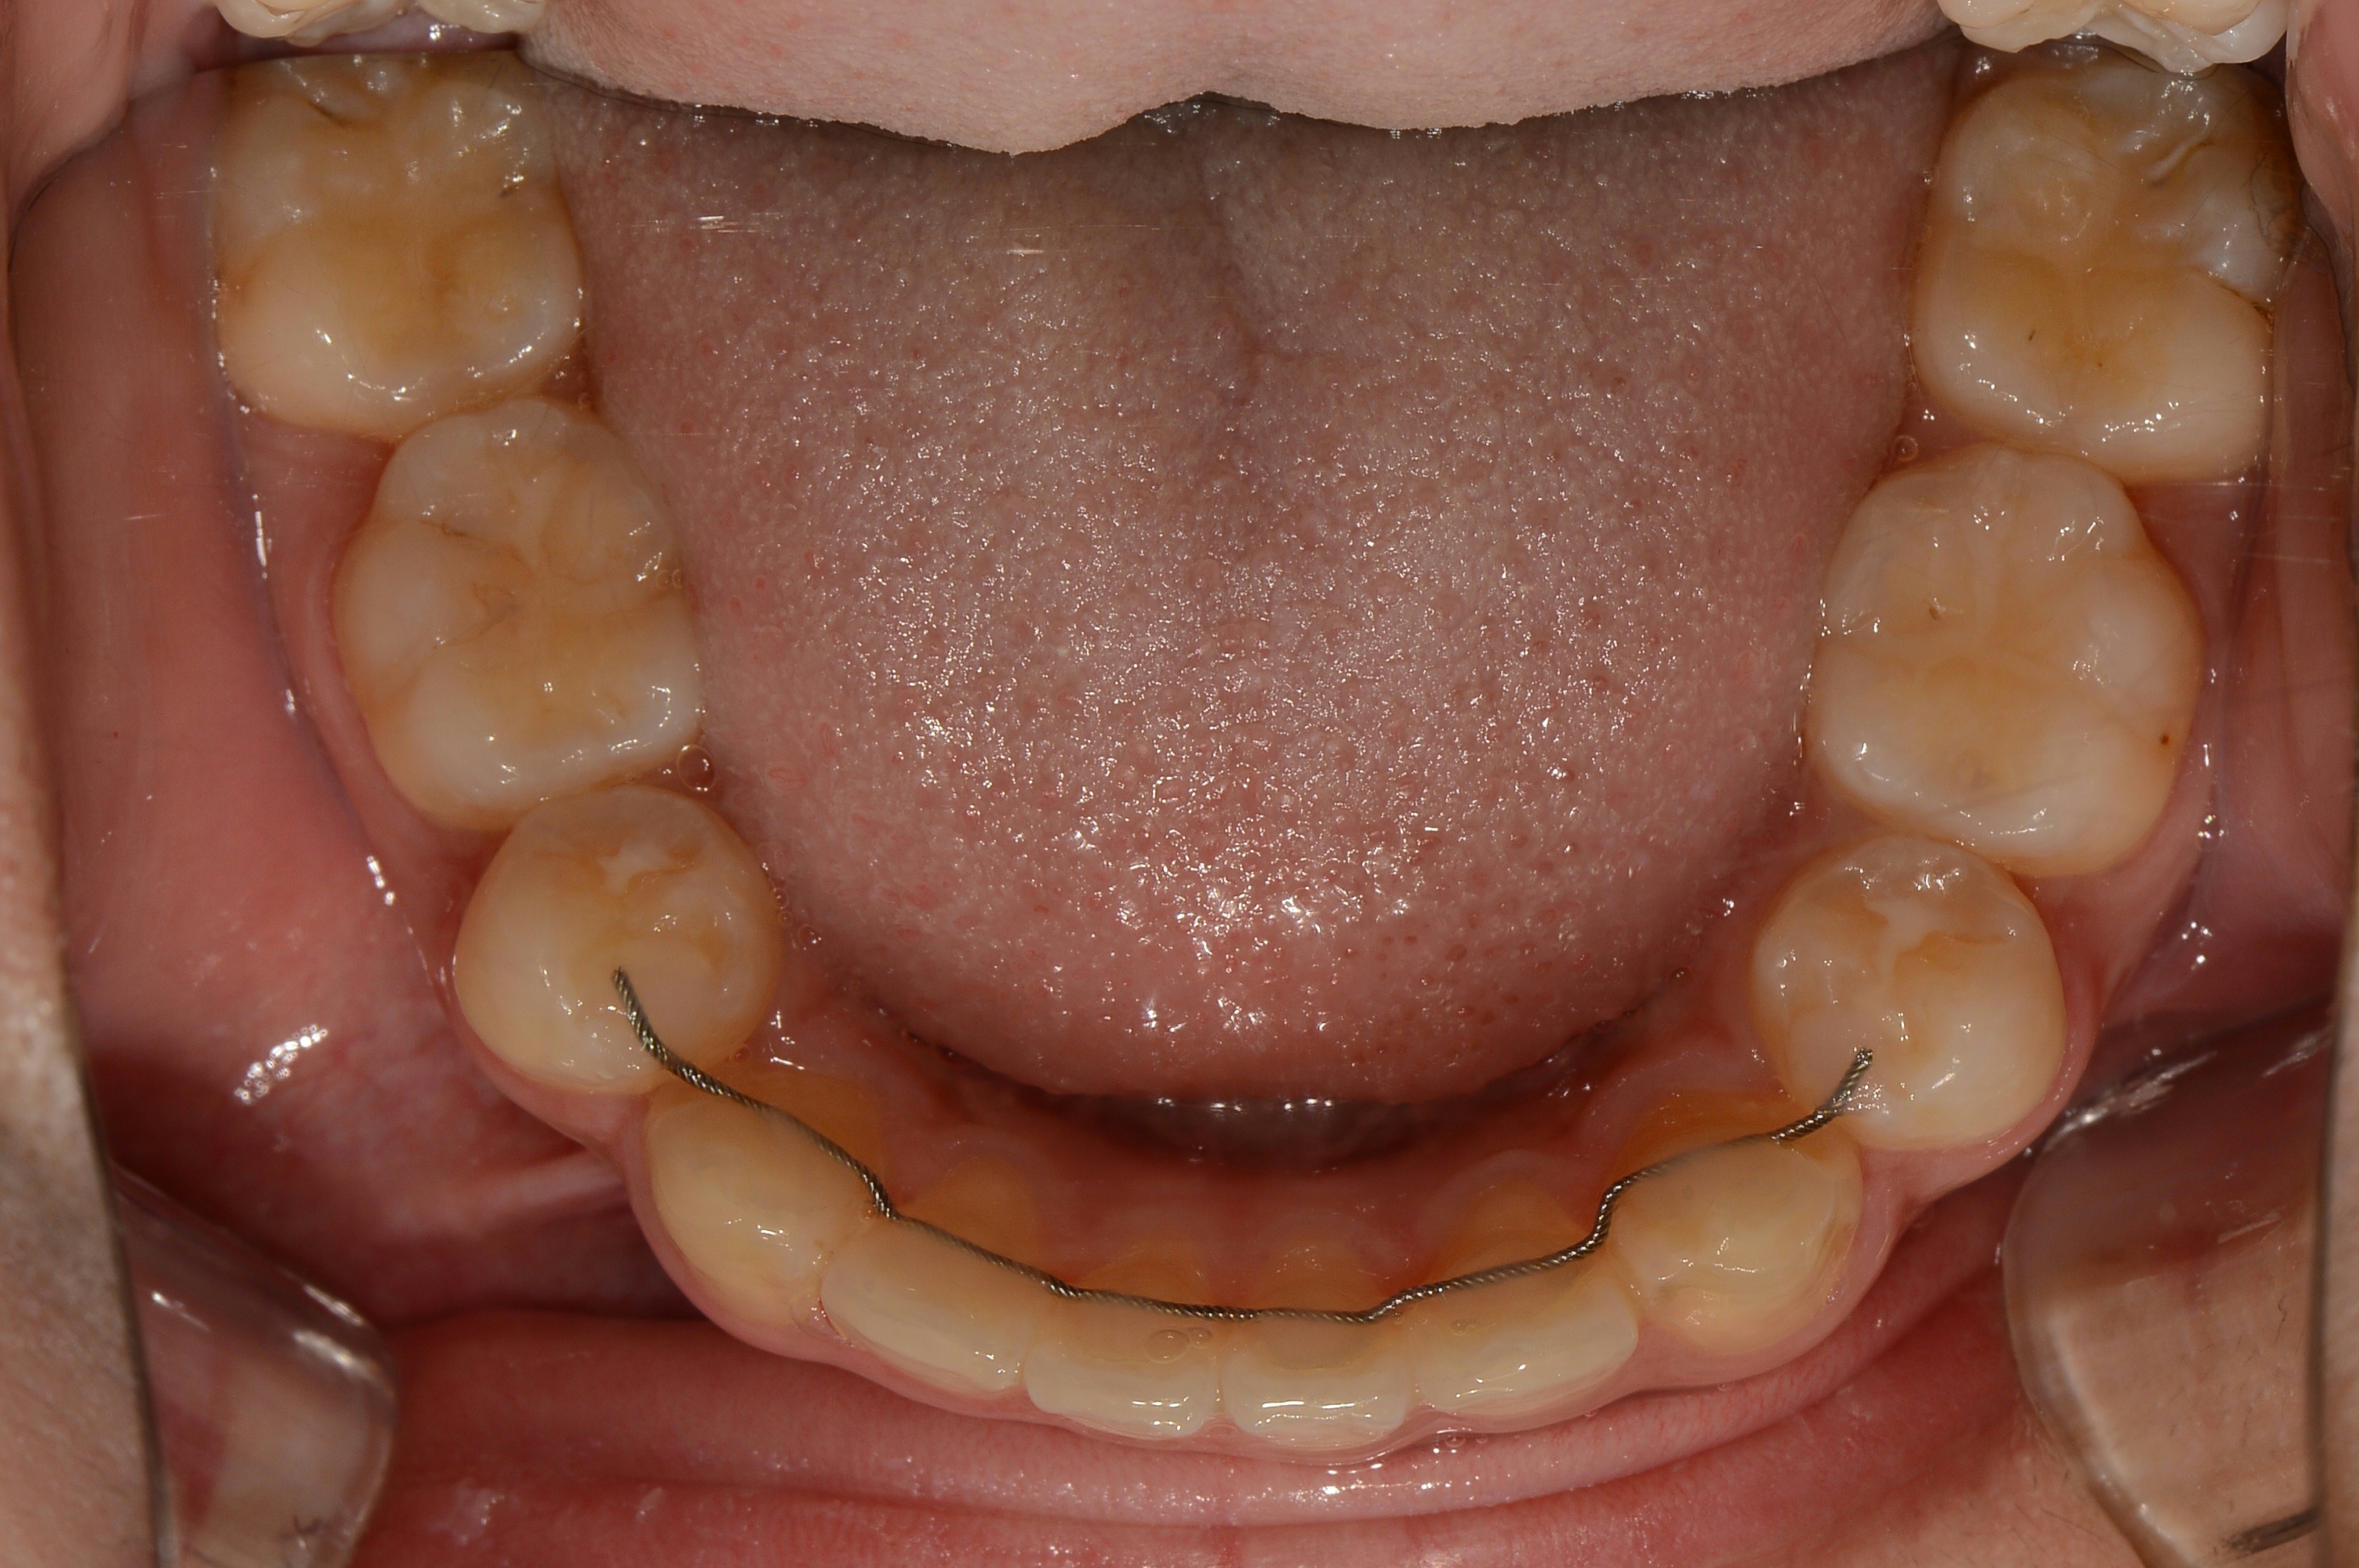

치료 후 사진입니다.